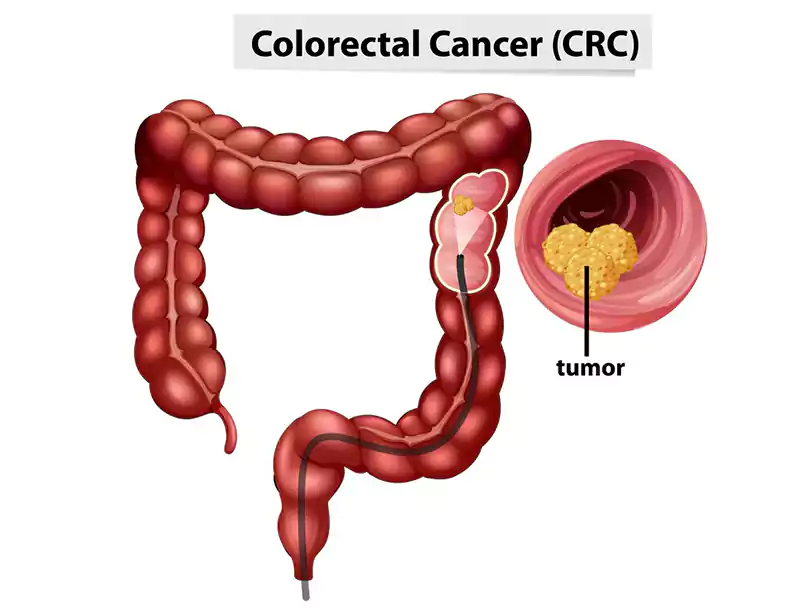

سرطان روده بزرگ و راستروده (CRC) تقریباً همیشه با پولیپهای پیشسرطانی یا تودههایی در روده بزرگ یا راستروده آغاز میشود. داشتن سن بالای ۵۰ سال، یکی از عوامل شناختهشده برای بروز این پولیپهای غیرطبیعی است بنابراین در واقع نباید آنقدر از نتیجه آزمایش متعجب میشدم.

برداشتن پولیپهای پیشسرطانی مانع از تبدیل آنها به سرطان میشود، اما تشخیص آنها بدون غربالگری ممکن نیست. روشهایی مانند کولونوسکوپی یا تستهای خانگی نقش مهمی در شناسایی این پولیپها دارند. هرچه تشخیص زودتر انجام شود، درمان مؤثرتر خواهد بود.

این روش رایجترین و کاملترین روش غربالگری است. پزشک با استفاده از یک لوله انعطافپذیر مجهز به دوربین، کل روده بزرگ و راستروده را بررسی میکند. در صورت مشاهده پولیپ یا رشد غیرطبیعی، امکان برداشت آنها به صورت همزمان وجود دارد.

این سرطان از رشد غیرطبیعی سلولها در روده بزرگ یا راستروده شروع میشود و در صورت تشخیص دیرهنگام میتواند به سایر بخشهای بدن گسترش یابد.